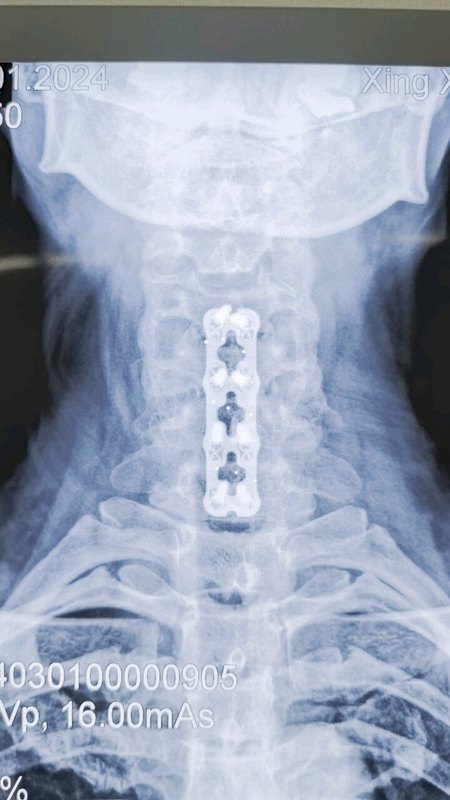

不少患者查出頸椎病后,發(fā)現(xiàn)不是頸椎受壓就是脊髓受壓,這兩種情況有什么不同呢?哪一種更嚴(yán)重呢?如果既壓迫到神經(jīng),又壓迫到脊髓,又該怎么辦呢?頸椎病壓到神經(jīng)和脊髓,有什么不同?事實上,這個問題是在對比神經(jīng)根型頸椎病和脊髓型頸椎病。頸椎病由于頸椎退化等各種原因?qū)е轮車纳窠?jīng)根、脊髓、血管等組織受壓,導(dǎo)致出現(xiàn)一系列癥狀。根據(jù)受壓組織不同,頸椎病又分為許多類型,其中最常見的就是神經(jīng)根型頸椎病,最嚴(yán)重的就是脊髓型頸椎病。顧名思義,神經(jīng)根型頸椎病常由于頸椎間盤突出等原因?qū)е律窠?jīng)根受壓,患者常會出現(xiàn)上肢的放射性疼痛、麻木、無力等癥狀;而脊髓型頸椎病壓迫到脊髓,患者除了上肢癥狀外,還會出現(xiàn)下肢的走路踩棉花感、走路不穩(wěn)等情況。這兩種類型的頸椎病治療方案也略有不同,神經(jīng)根型頸椎病多數(shù)情況下保守治療就可以了,只有患者的病情嚴(yán)重,保守治療無效,嚴(yán)重影響生活了才會考慮手術(shù)干預(yù)。但脊髓型頸椎病是一旦確診就需要盡快手術(shù)的,保守治療效果不好,而且脊髓長時間受壓,可能會導(dǎo)致一些不可逆的功能障礙。既壓到神經(jīng),又壓到脊髓,這種頸椎病要怎么辦?最近,宣武醫(yī)院王作偉主任接診了一位44歲的女性頸椎病患者。這位患者出現(xiàn)脖子疼痛、僵硬已經(jīng)有3年了,難受的時候會做熱敷、針灸,但在2個月前,她的右側(cè)上肢出現(xiàn)了放射性疼痛,麻木乏力,偶爾時不時還會出現(xiàn)走路腳底有踩棉感,這讓她非常難受,去了當(dāng)?shù)蒯t(yī)院檢查出頸椎病?;颊邽榱诉M(jìn)一步治療,最后找到王主任。從她的片子、查體等檢查結(jié)果上看,她的頸椎生理曲度消失,甚至有點反弓,而且在頸4-7多個節(jié)段出現(xiàn)了椎間盤突出,突出不僅壓迫到了神經(jīng)根,同時也壓迫到了脊髓。這種情況該怎么辦?這樣的情況,王主任建議進(jìn)行手術(shù)治療。兩者都受到壓迫,尤其是她出現(xiàn)脊髓受壓,并出現(xiàn)下肢走路問題,這時保守治療已經(jīng)沒有太大效果,這種情況還是要盡快手術(shù)處理。術(shù)前影像學(xué)資料:在獲得患者和家屬的同意后,王主任為她成功進(jìn)行了手術(shù)治療。手術(shù)對突出的椎間盤進(jìn)行了切除,給神經(jīng)根和脊髓進(jìn)行了徹底減壓,并給頸椎進(jìn)行內(nèi)固定,重建了穩(wěn)定性。術(shù)后,患者的上肢疼痛立馬得到極大緩解,不到第3天,她就已經(jīng)可以戴著頸托獨自行走了,其余的麻木、乏力癥狀也在逐漸好轉(zhuǎn)。術(shù)后影像學(xué)資料:最后,不管您是神經(jīng)根受壓、脊髓受壓,還是兩個都受壓,出現(xiàn)類似上面這些癥狀時,都要及時去醫(yī)院檢查。若單純是神經(jīng)根型頸椎病,對生活影響不大,建議您先保守治療;若是壓到脊髓或兩個都壓到了,就要考慮盡快手術(shù)干預(yù)了。